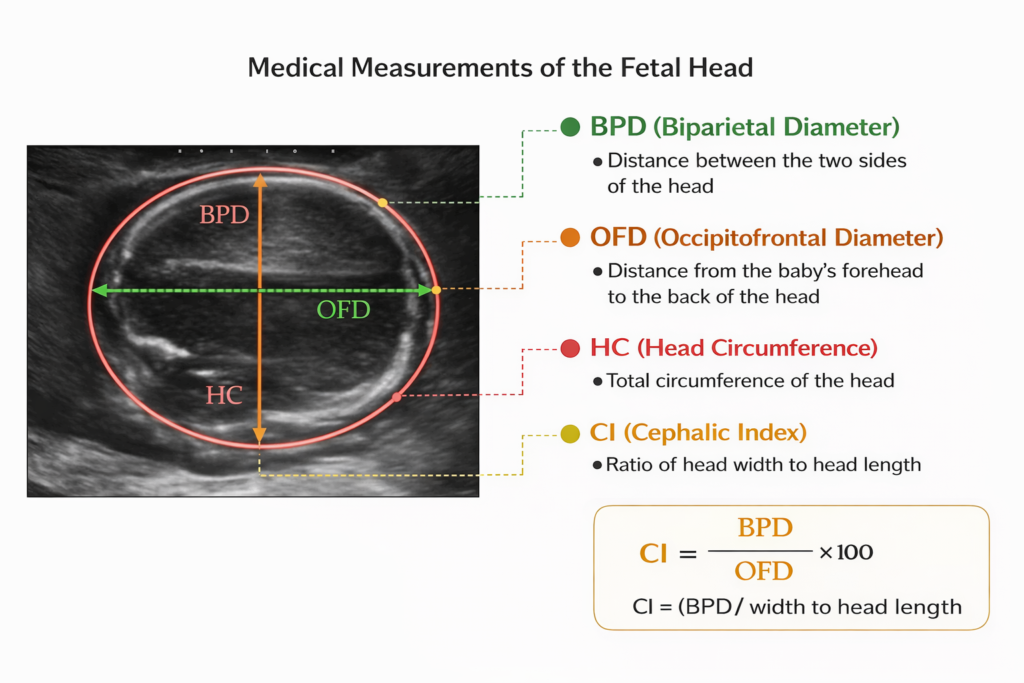

This project focuses on automated fetal head analysis using ultrasound images to support early prenatal screening. It uses deep learning–based segmentation to accurately extract the fetal head region and automatically compute key biometric parameters such as Biparietal Diameter (BPD), Occipitofrontal Diameter (OFD), Head Circumference (HC), and Cephalic Index. By combining these measurements with CNN-based image features, the system classifies fetal head development as normal or abnormal, reducing operator dependency and improving reliability in detecting fetal head abnormalities.

the fetal head region and automatically compute key biometric parameters such as Biparietal Diameter (BPD), Occipitofrontal Diameter (OFD), Head Circumference (HC), and Cephalic Index.

- To automatically compute key fetal head biometric parameters from the segmented region, including Biparietal Diameter (BPD), Occipitofrontal Diameter (OFD), Head Circumference (HC), Cephalic Index (CI)

4.Head Parameter Extraction

After segmentation, geometric methods are applied to extract fetal head parameters:

- Head Circumference (HC)

- Biparietal Diameter (BPD)

• The segmented head region is then used for computing BPD, OFD, HC and Cephalic Index with improved reliability.